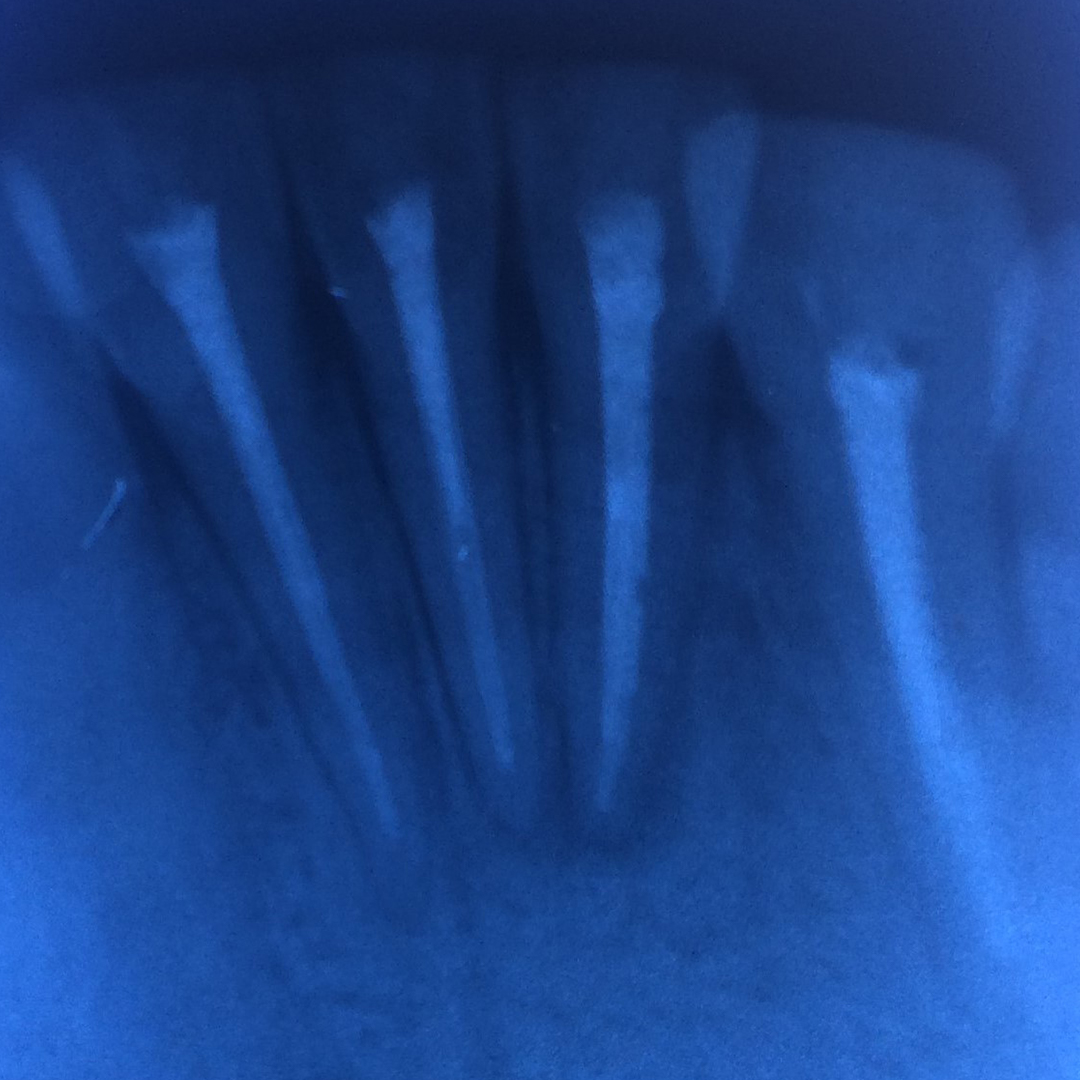

До и после лечения

Пациент обратился в «Стоматологию Комфорта» с жалобой на острую боль в области нижних резцов, возникшую после начала лечения в другой клинике. В ходе осмотра и по результатам диагностики врач стоматолог-терапевт Вахлюева Елена Сергеевна поставила диагноз — периодонтит в стадии обострения.

В процессе лечения проведены следующие манипуляции:

- эндодонтическое лечение зубов 3.1, 3.2, 4.1, 4.2;

- пломбировка корневых каналов;

- временное восстановление коронковой части зубов.